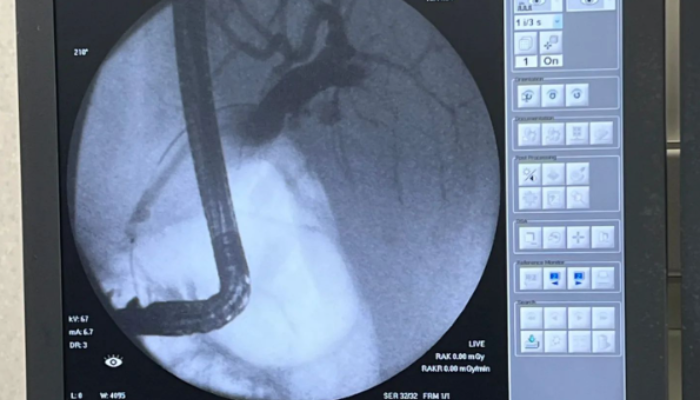

El Hospital de Minas ha alcanzado un hito significativo en el campo de la medicina con la exitosa realización de una colangiopancreatografía retrógrada endoscópica (CPRE). Este procedimiento innovador, que combina la endoscopia gastrointestinal de la parte superior del aparato digestivo y las radiografías, se utiliza para tratar problemas relacionados con los conductos biliares y pancreáticos.

La CPRE se utiliza para diagnosticar y tratar afecciones como cálculos biliares, estenosis de los conductos biliares, tumores y pancreatitis. Al combinar la endoscopia con las radiografías, los médicos pueden visualizar con precisión los conductos biliares y pancreáticos, y realizar intervenciones terapéuticas cuando sea necesario.